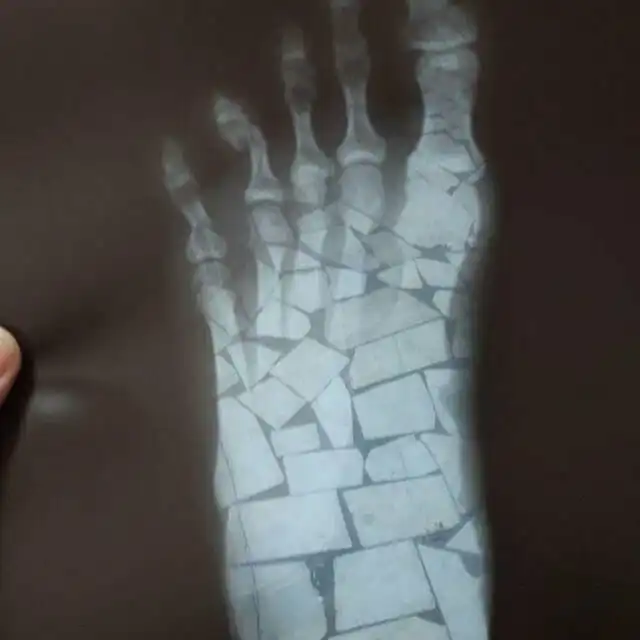

Пациент выслал фото врачу. Тот долго не мог понять, что со стопой

Просто выбирайте нормальный фон!